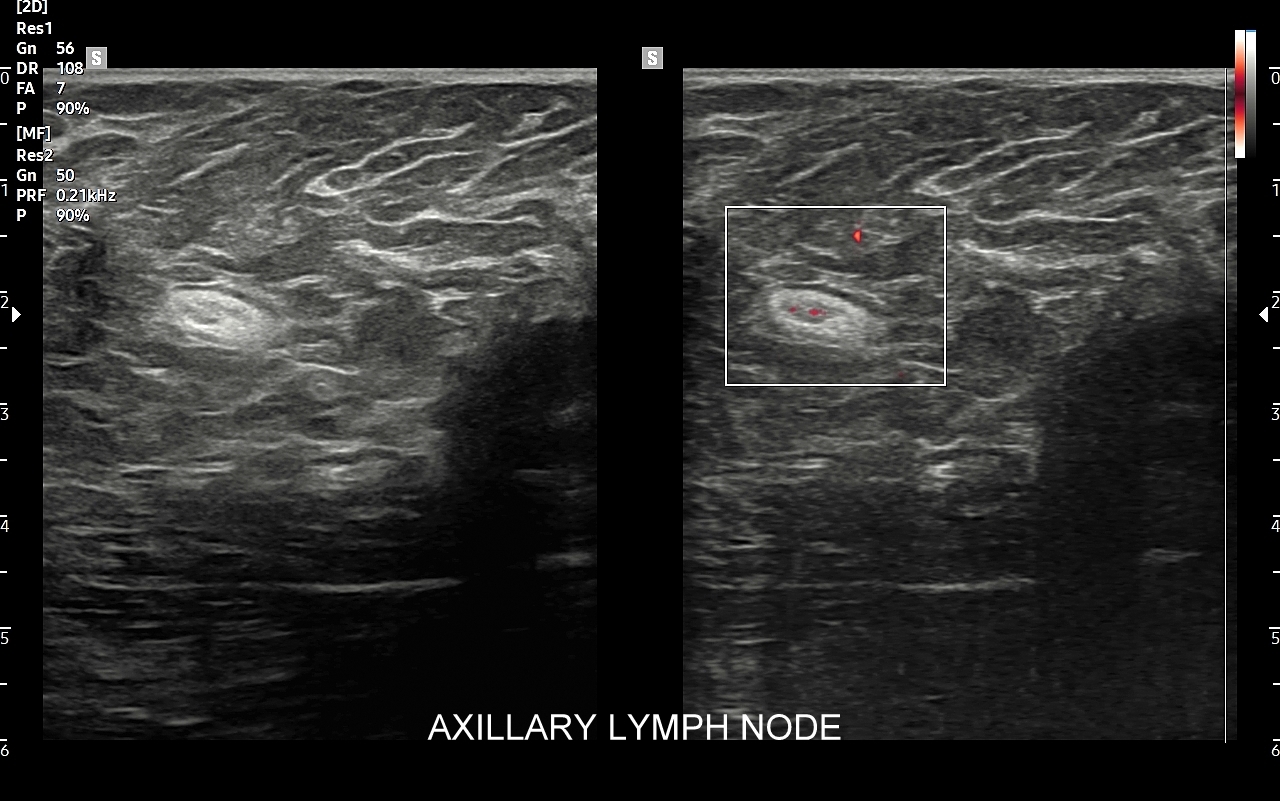

Badanie USG jest podstawową metodą obrazowania węzłów chłonnych. W jego trakcie ocenia się nie tylko wielkość węzłów, lecz także ich kształt, proporcje wymiarów, morfologię, czyli wygląd zewnętrzny oraz strukturę wewnętrzną, ich unaczynienie, spoistość, a także tkanki otoczające. W trakcie interpretacji badania pod uwagę bierze się również zbierany od pacjenta wywiad chorobowy oraz wyniki innych badań obrazowych i laboratoryjnych takich jak morfologia, OB, CRP, żelazo, ferrytyna, TIBC, innych parametrów infekcyjnych, a także onkologicznych. Ultrasonografia węzłów chłonnych jest procedurą bezpieczną i dokładną. W Pracowni dr Szczepańskiego węzły chłonne oceniane są nowoczesną metodą MPUS (multiparametryczne badanie USG), w szczególności z zastosowaniem trybów mikrounaczynienia i elastografii.

Do powiększenia węzłów chłonnych szyi, stanu określanego jako limfadenopatia, dochodzi najczęściej w przebiegu chorób zakaźnych górnych dróg oddechowych, wirusowych i bakteryjnych. Inne przykłady przyczyn limfadenopatii szyjnej obejmują ropne choroby zębów, migdałków i zatok przynosowych; odczyny w chorobach autoimmunologicznych, np. w chorobie Hashimoto i Sjögrena; a także rozrostowe schorzenia układu hematologicznego (białaczki i chłoniaki) i choroby nowotworowe jak np. rak tarczycy, krtani, migdałka, czy języka. Należy mieć na uwadze, iż w przypadku podejrzenia chorób układu krwiotwórczego oraz mononukleozy zakaźnej, oprócz węzłów chłonnych, niezbędne jest również badanie USG wątroby i śledziony. W części przypadków, gdy podejrzewa się możliwość choroby nowotworowej lub w celu jej wykluczenia, lekarz może zalecić rozszerzenie diagnostyki obrazowej na inne obszary ciała.